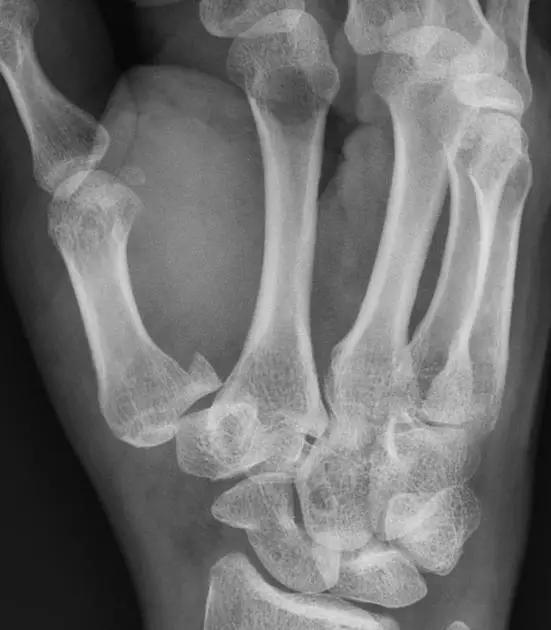

6. Bennett 骨折

第 1 掌骨基底的斜形骨折,掌骨近端形成轴向移位,掌侧边缘形成三角形的骨碎片。

(来源:Radiopaedia)